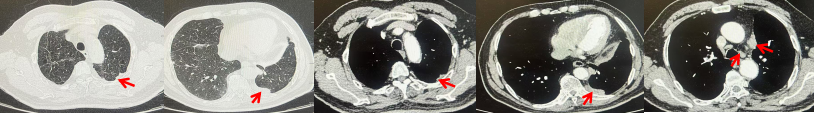

69岁男性,无糖尿病、高血压、心脏病等基础疾病,无吸烟、饮酒史,无肿瘤家族史。2023.06.07行胸部CT检查:右肺上叶胸膜下见肿物影,大小约33mm×22mm,边缘可见分叶,考虑恶性病变可能性大,双肺间质改变(如图1)。2023.06.14行“单孔胸腔镜下右肺上叶切除、肺门及纵隔淋巴结清扫、胸膜粘连松解术”;术后病理:(右肺上叶)腺癌(低分化,实体型占60%,不良腺体占40%),局灶伴神经内分泌标记表达(CD56、Syn),可见STAS及胸膜侵犯,未见确切神经侵犯及脉管内癌栓;(气管切缘)净;(淋巴结)未见转移癌0/26(2组0/2;4组0/6;7组0/2;对侧7组0/8;10组0/2;11组0/3;12组0/2;13组0/1)。术后分期pT2aN0M0 IB期,术后NGS基因检测:无驱动基因突变,PD-L1(22C3)TPS<1%。术后定期复查。

图1:患者手术前(2023.06)胸部CT肺窗及纵隔窗